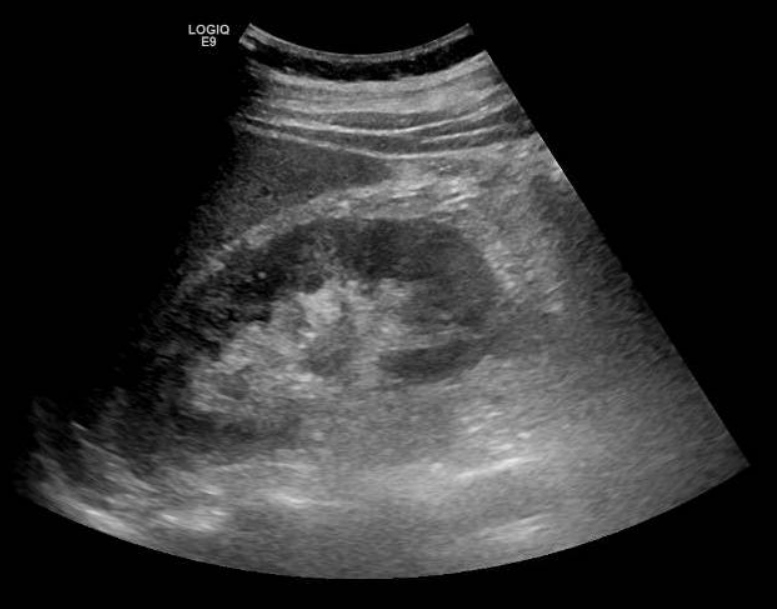

Se solicita ecografía abdominal que muestra líquido en espacio pararrenal posterior derecho bajo, sobre músculo psoasilíaco derecho, y leve ectasia piélica derecha sin identificar causa.

Entre las entidades que afectan al espacio pararrenal nos encontramos linfangioma, entidades fibróticas, hematomas, abscesos, neoplasias… Por tanto, se completa estudio con TAC abdominal con contraste. En el TAC se observa litiasis de 3 mm en meato ureteral derecho con dilatación pielocalicial grado II y leve-moderada cantidad de líquido en espacios retroperitoneales peri y pararrenal derechos, que se relacionan con salida de contraste intravenoso en fase excretora, compatible con rotura de la vía urinaria sin identificarse claro punto de fuga.